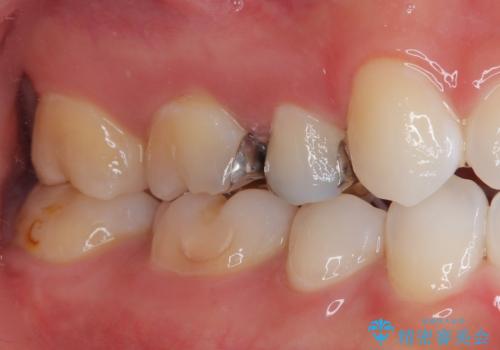

手前の銀歯は患者様のご希望によりやり替えをしていません。

見た目、機能面共に大変喜んでいただきました。